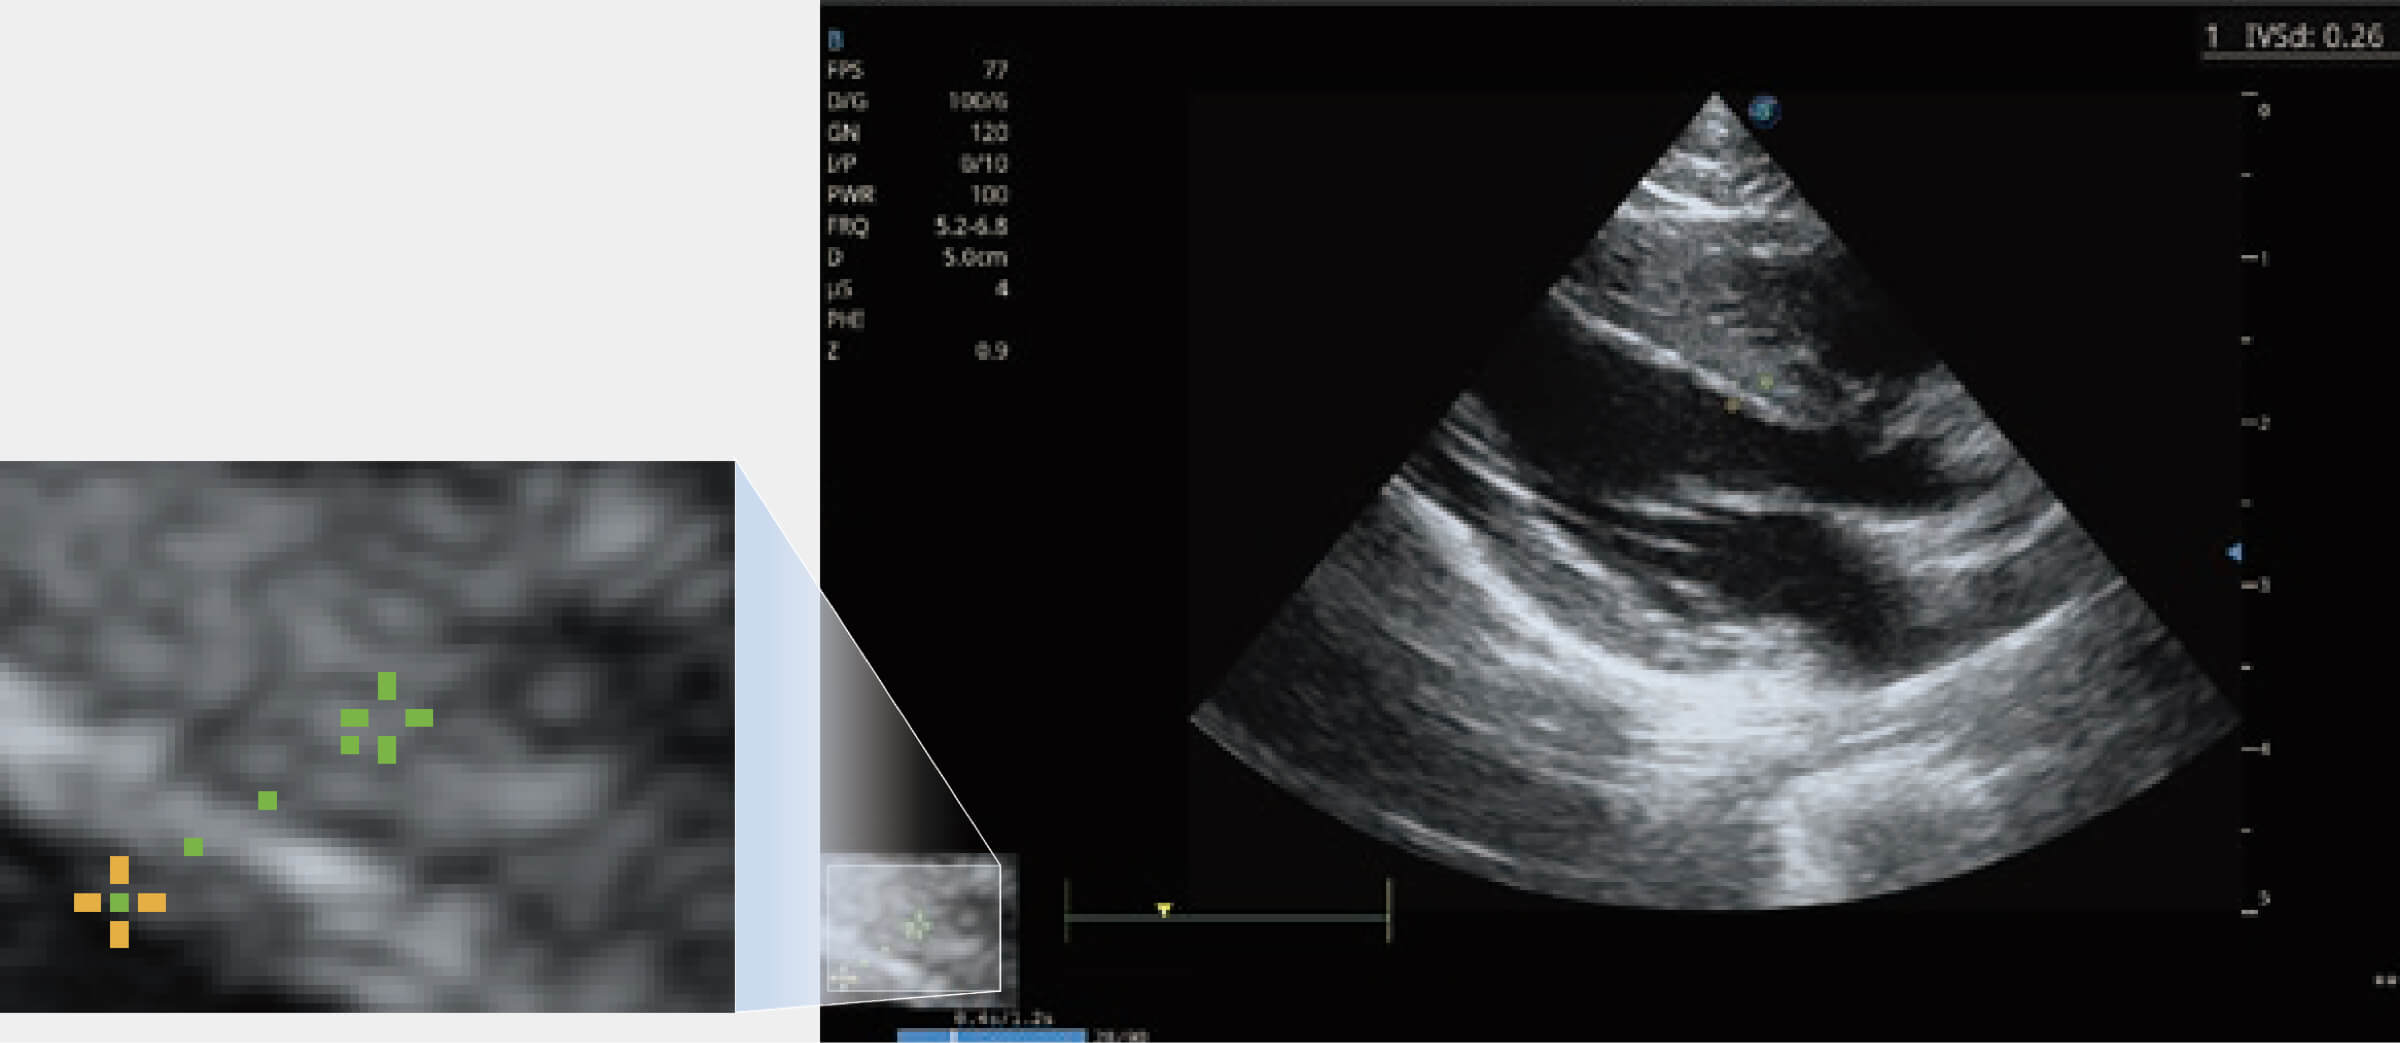

通過心肌識別技術(shù)與二維斑點(diǎn)追蹤技術(shù)相結(jié)合,對心臟的超聲圖像進(jìn)行量化分析。計算心肌17個節(jié)段的應(yīng)變、應(yīng)變率、速度、位移等,并通過牛眼圖的形式進(jìn)行呈現(xiàn)。

能夠基于左心室壁追蹤和辛普森法,自動計算射血分?jǐn)?shù),支持多個可移動點(diǎn)描跡,與手動測量相比,極大節(jié)省了動物醫(yī)生的時間和精力。